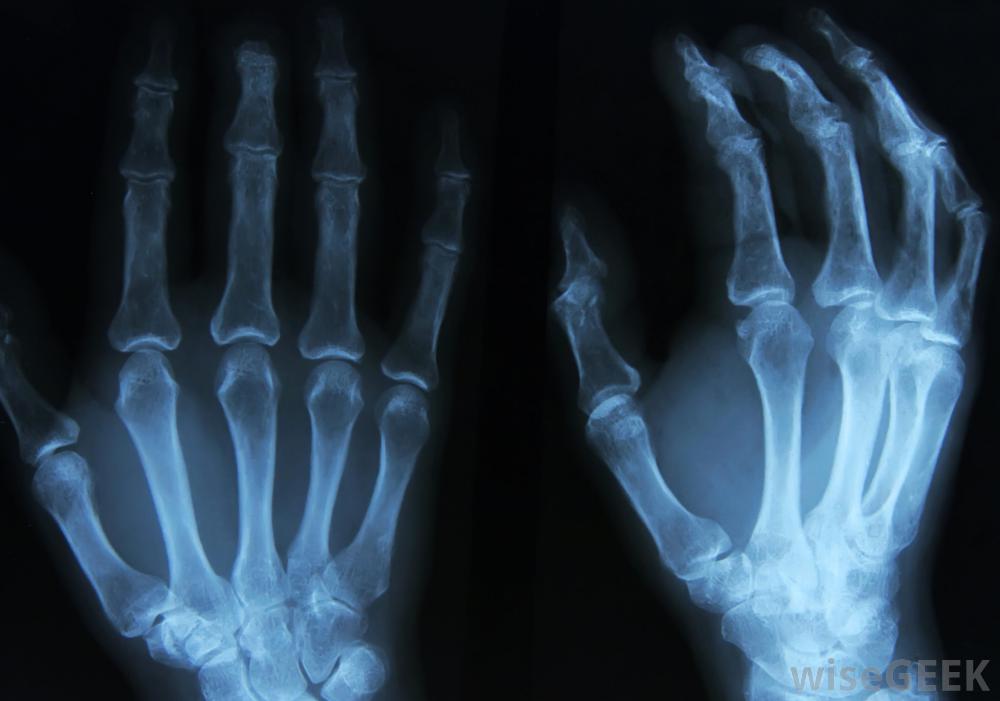

內生軟骨瘤是一種良性腫瘤,出現在骨骼內的軟骨組織中。在大多數情況下,內生軟骨瘤無痛,不會導致任何不良的生理癥狀。然而,當腫瘤異常大或有多個腫瘤時,一個人可能患有骨折或畸形。內生軟骨瘤最有可能出現在手或腳的小骨中,盡管它們可能會影響身體的任何部位。治療很少需要,最常見的手術包括手術切除腫瘤和修復受損的骨組織如果醫生懷疑內生軟骨瘤導致骨折,可以進行X光檢查不清楚為什么會出現內生軟骨瘤,但可能是胚胎軟骨在已經發育好的骨骼內不斷生長的結果。這種軟骨瘤最常見于10至20歲的兒童和青少年,在男性和女性中出現的比率幾乎相同。內生軟骨瘤通常無痛,不會被發現,除非醫生在對其他損傷或情況進行診斷測試時會注意到這一點。當切除腫瘤時,將使用手術刀刮除內生軟骨瘤腫瘤有時會長得足夠大,給骨頭施加壓力并導致骨折來自內生軟骨瘤的持續壓力也會導致手或腳的畸形。有時,多發性內生軟骨瘤存在于一塊骨頭內,稱為Ollier~s病。Maffucci~s綜合征與骨軟骨瘤伴血管瘤的情況相似。Ollier~s病和Maffucci~s綜合征均可引起慢性疼痛、骨折和畸形如果醫生懷疑內生軟骨瘤導致骨折或畸形,他或她通常會采取x光片,磁共振成像(MRI)掃描,或其他影像學檢查來確認診斷。當MRI或x光結果顯示內生軟骨瘤時,醫生會根據大小、位置決定最佳治療措施,對醫生來說,仔細檢查骨腫瘤以確保它們沒有癌變的跡象是很重要的。手術固定骨折或變形的骨頭通常足以防止將來小范圍的不良反應內生軟骨瘤。大的腫瘤通常在精細的外科手術中被切除,包括用手術刀刮去內生軟骨瘤,并將新的組織移植到骨上。病人通常需要在手術后回到醫生的辦公室進行常規的核磁共振掃描,以監測骨愈合情況腫瘤復發,雖然一個內生軟骨瘤的人可能在身體的不同部位有其他未被發現的腫瘤當X光檢查結果顯示內生軟骨瘤時,醫生將根據腫瘤的大小和位置決定最佳治療方法。